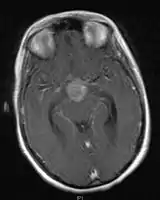

CNS Germinoma

- Mainly located in midline structures, suprasellar region or pineal gland, also basal ganglia and hypothalamus

- Pineal Gland Germinoma

- Suprasellar Germinoma